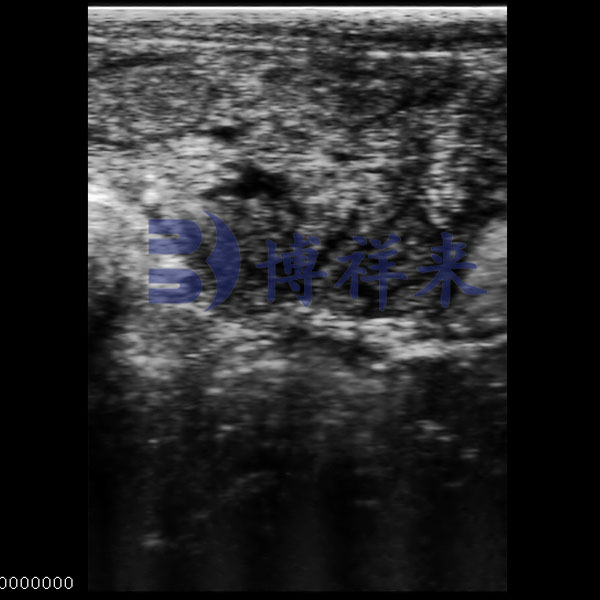

Ovarian Follicle Ultrasound

● Displays multiple follicle cavities of varied shapes.

● Layered echoes for structural recognition.

● Shows cavity distribution and size.

● For reproductive monitoring in livestock.